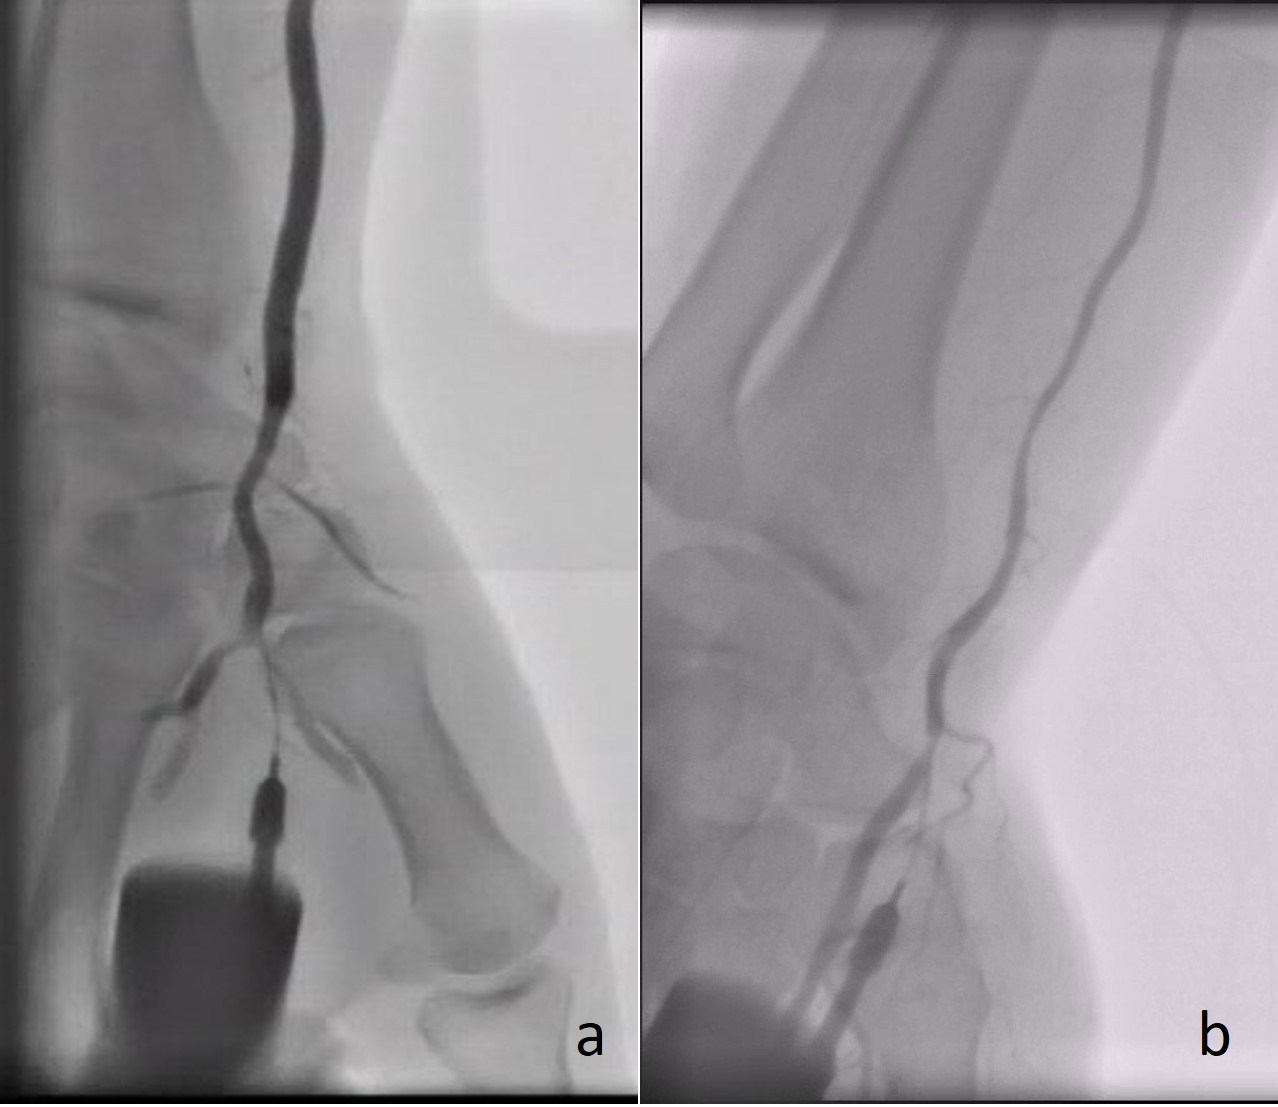

Fig. 2.Angiography demonstrating the radial artery using a plastic catheter directly after successful puncture of the (a) rDB and (b) rSB.